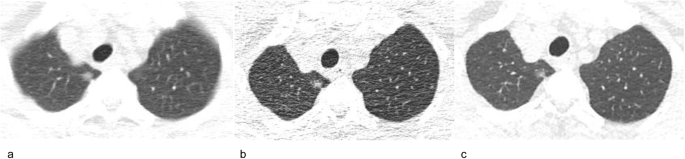

A 70-year-old man with a stable subsolid nodule after long-term follow-up CT. a Transverse plain CT section of a part-solid nodule in the right upper lobe. The nodule size (longest diameter) was 9 mm on transverse CT images at baseline. b Follow-up CT obtained 5 years after baseline showed that the nodule is stable. c The nodule was still stable after a 10-year follow-up